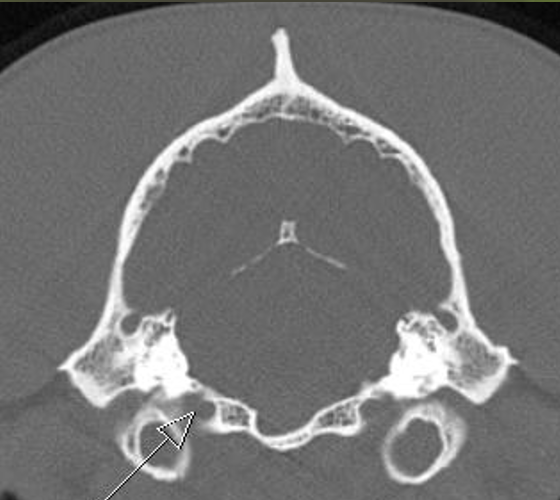

hypoglossal canal